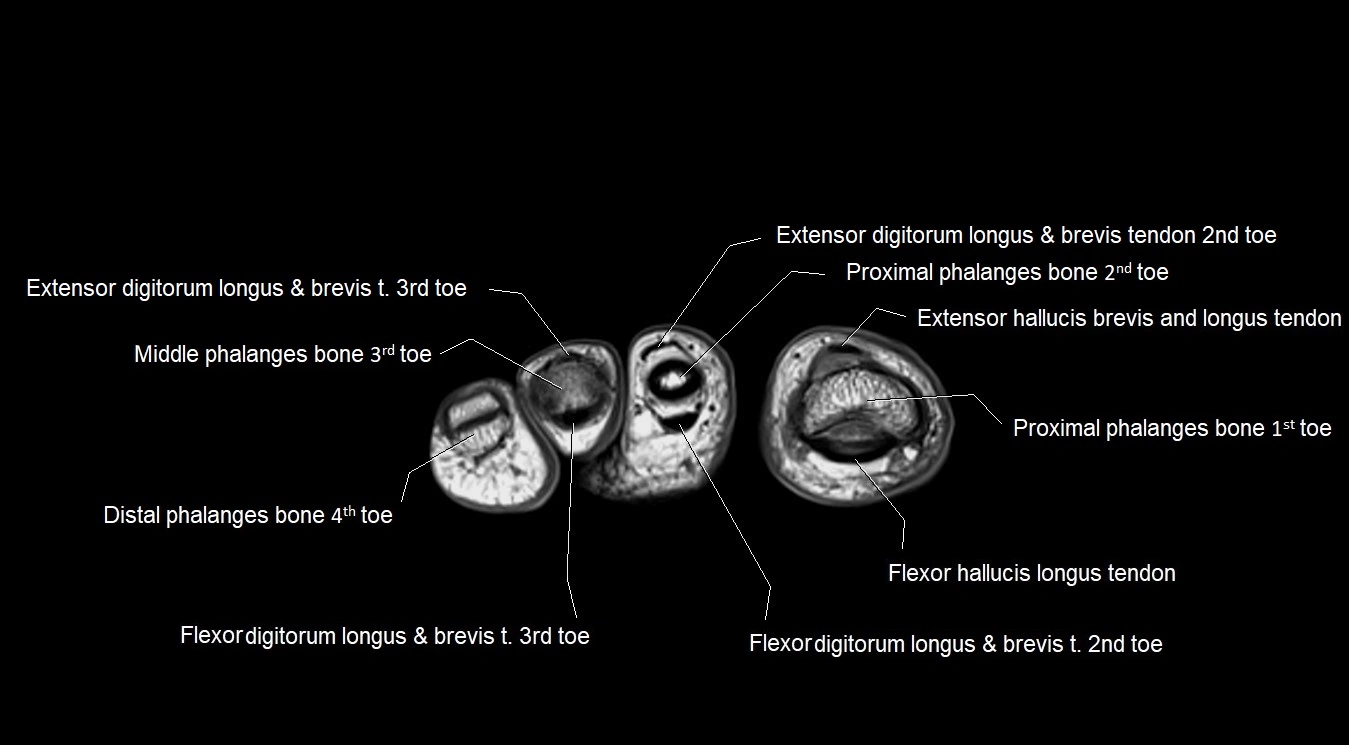

MRI image